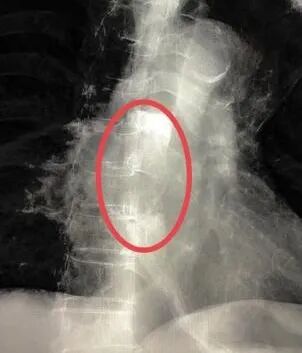

普外科主任周志伟通过详细询问患者病史、全面体格检查、查阅相关CT及胃镜检查报告,鉴于患者年龄大、体质弱、营养状况差等因素,开启绿色通道将患者收住院。经过医院多学科专家联合会诊,确定了为患者施行“食道支架植入术的微创治疗”方案。此次手术在DSA引导下进行,普外科专家团队用精湛娴熟的操作技术,经口把食道支架成功放置到病灶部位,整个手术历时30分钟,期间患者无明显不适。

普外科主任周志伟介绍,我国是消化道肿瘤高发国家,每年食道癌、胃癌、结肠癌、直肠癌都会造成较高的死亡率。消化道肿瘤往往会造成消化道阻塞,影响进食或排便,而食道癌最大的问题是患者进食困难。此次市五院开展的食道支架植入术是针对各种原因引起的食道狭窄进行扩张后放置内支架的技术。手术选用的支架具有良好的生物相容性和耐腐蚀性,同时具有记忆特性和超弹性,可使梗阻部位恢复通畅。另外,支架表面覆有医用硅橡胶膜,可有效防止食管壁肿瘤进入支架内。通过开展此项新技术,帮助肿瘤患者陈伯减轻了痛苦,提高了生活质量,延长了生命周期。今后,可让周边此类患者就近得到标准化、高质量的医疗服务。